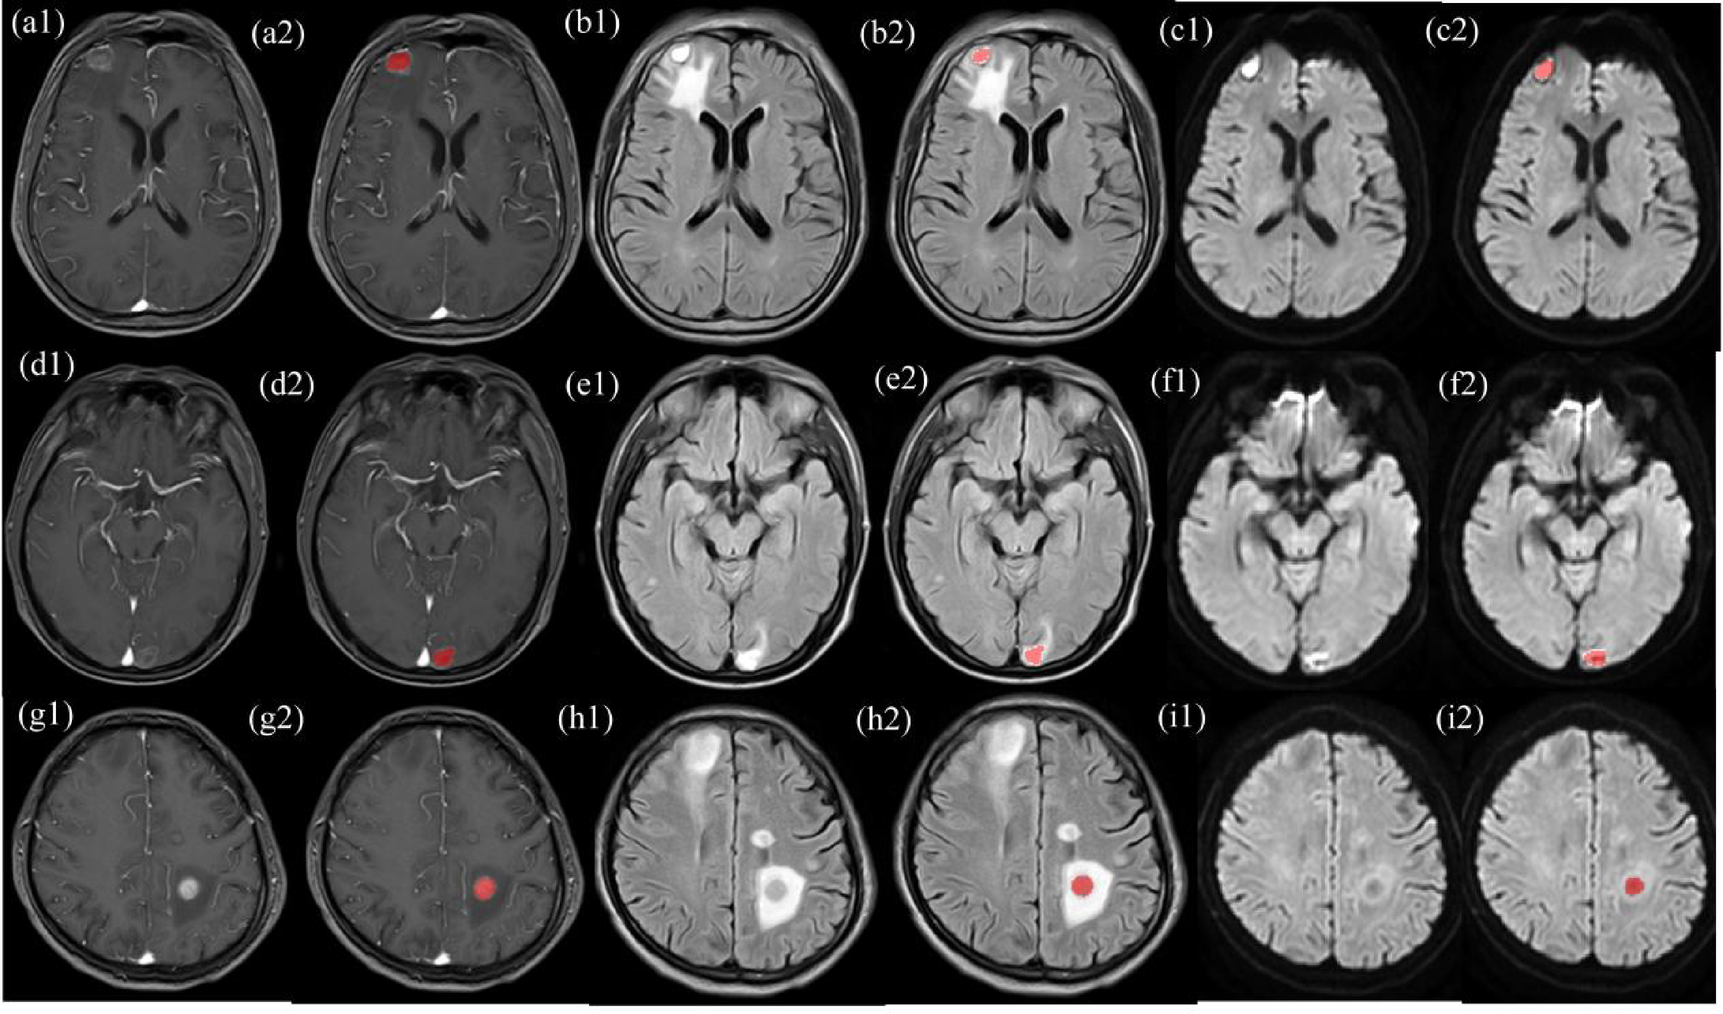

Fig. 2

Delineation of ROIs in T1-weighted imaging (T1WI) (a1–2, d1–2, g1–2), T2-fluid-attenuated inversion recovery (T2-FLAIR) (b = 800) (b1–2, e1–2, h1–2), and diffusion-weighted imaging (DWI) (c1–2, f1–2, i1–2). a1–2, b1–2, c1–2: man, 66 years old, with BMs in SCLC. a1, b1, and c1 represent the original lesions, and a2, b2, and c2 show the lesions after ROI delineation. d1–2, e1–2, f1–2: man, 45 years old, with BMs in AD. d1, e1, and f1 represent the original lesions, and d2, e2, and f2 depict the lesions after ROI delineation. g1–2, h1–2, i1–2: man, 49 years old, with BMs in NAD. g1, h1, and i1 represent the original lesions, and g2, h2, and i2 display the lesions after ROI delineation.